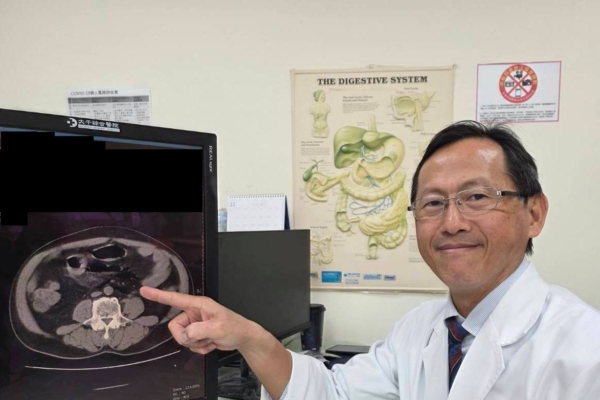

外科部主任馮啟彥緊急進行腹腔鏡手術,術中發現直腸上端靠近乙狀結腸的轉彎處,有一個直徑兩公分的破洞,研判應是太用力灌腸造成的腸道破裂。而這個破洞也讓大量的宿便流進腹腔,才會引發嚴重的腹膜炎。所幸,病人在接受手術後順利康復,也嚇得直呼「再也不敢自己隨意灌腸了!」。